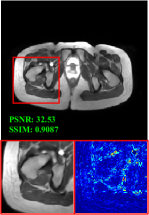

Figure 5 provides the qualitative comparison of the various methods on the four datasets at a scale of 4. The top, second, third, and bottom rows are the SR results under the FastMRI, clinical brain, clinical tumor and clinical pelvic datasets, respectively. The red boxes indicate the zoom-in region of complicated anatomical structures along with their corresponding error maps. Note that the brighter textures in the error maps, the lower the quality of the reconstructed images. As can be seen, compared to methods based on Transformers and CNNs, diffusion-based methods like DisC-Diff and DiffMSR (Ours) are capable of reconstructing high-realistic images with promising reconstruction metric scores (PSNR and SSIM). Nevertheless, while DisC-Diff can reconstruct high-precision MR images, it does not preserve the structure present in the original HR images, introducing some additional information that can affect medical diagnosis. In contrast, our method combines DM and PLWformer, which can preserve the original image’s structure while restoring high-frequency information.

In this section, we present more visual qualitative comparisons. Figures 8, 9, 10, and 11 show the reconstruction results of each method in FastMRI, clinical brain, clinical tumor, and clinical pelvic, respectively. As can be seen, although DisC-Diff can reconstruct MR images with high-frequency information, it fails to preserve the structure and content of the original Target HR image effectively, resulting in image distortion. In contrast, our proposed DiffMSR can restore high-frequency information while preserving the structure of the original HR image, indicating the effectiveness of the joint use of DM and PLWformer.